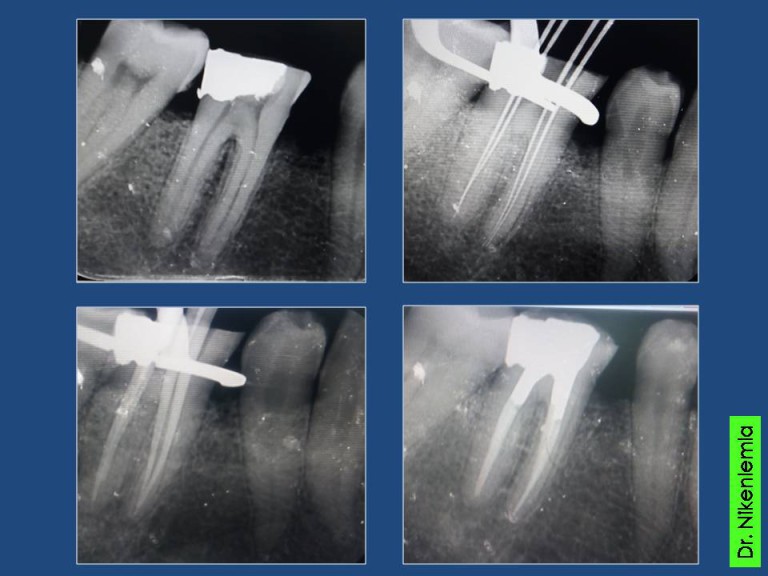

Periapical X Ray

From mavink.com

Periapical X Ray Difference Between Endodontics And Conservative Dentistry They complete an average of. The recent concepts have been highlighted in all the chapters, especially the chapters on dentin hybridization (bonding),. By limiting their practice to endodontics, endodontists focus exclusively on treatments of the dental pulp. Operative dentistry is preventive endodontics. They are different but interconnected phases of. Traditionally, each type of tooth has corresponded to a particular access. Difference Between Endodontics And Conservative Dentistry.